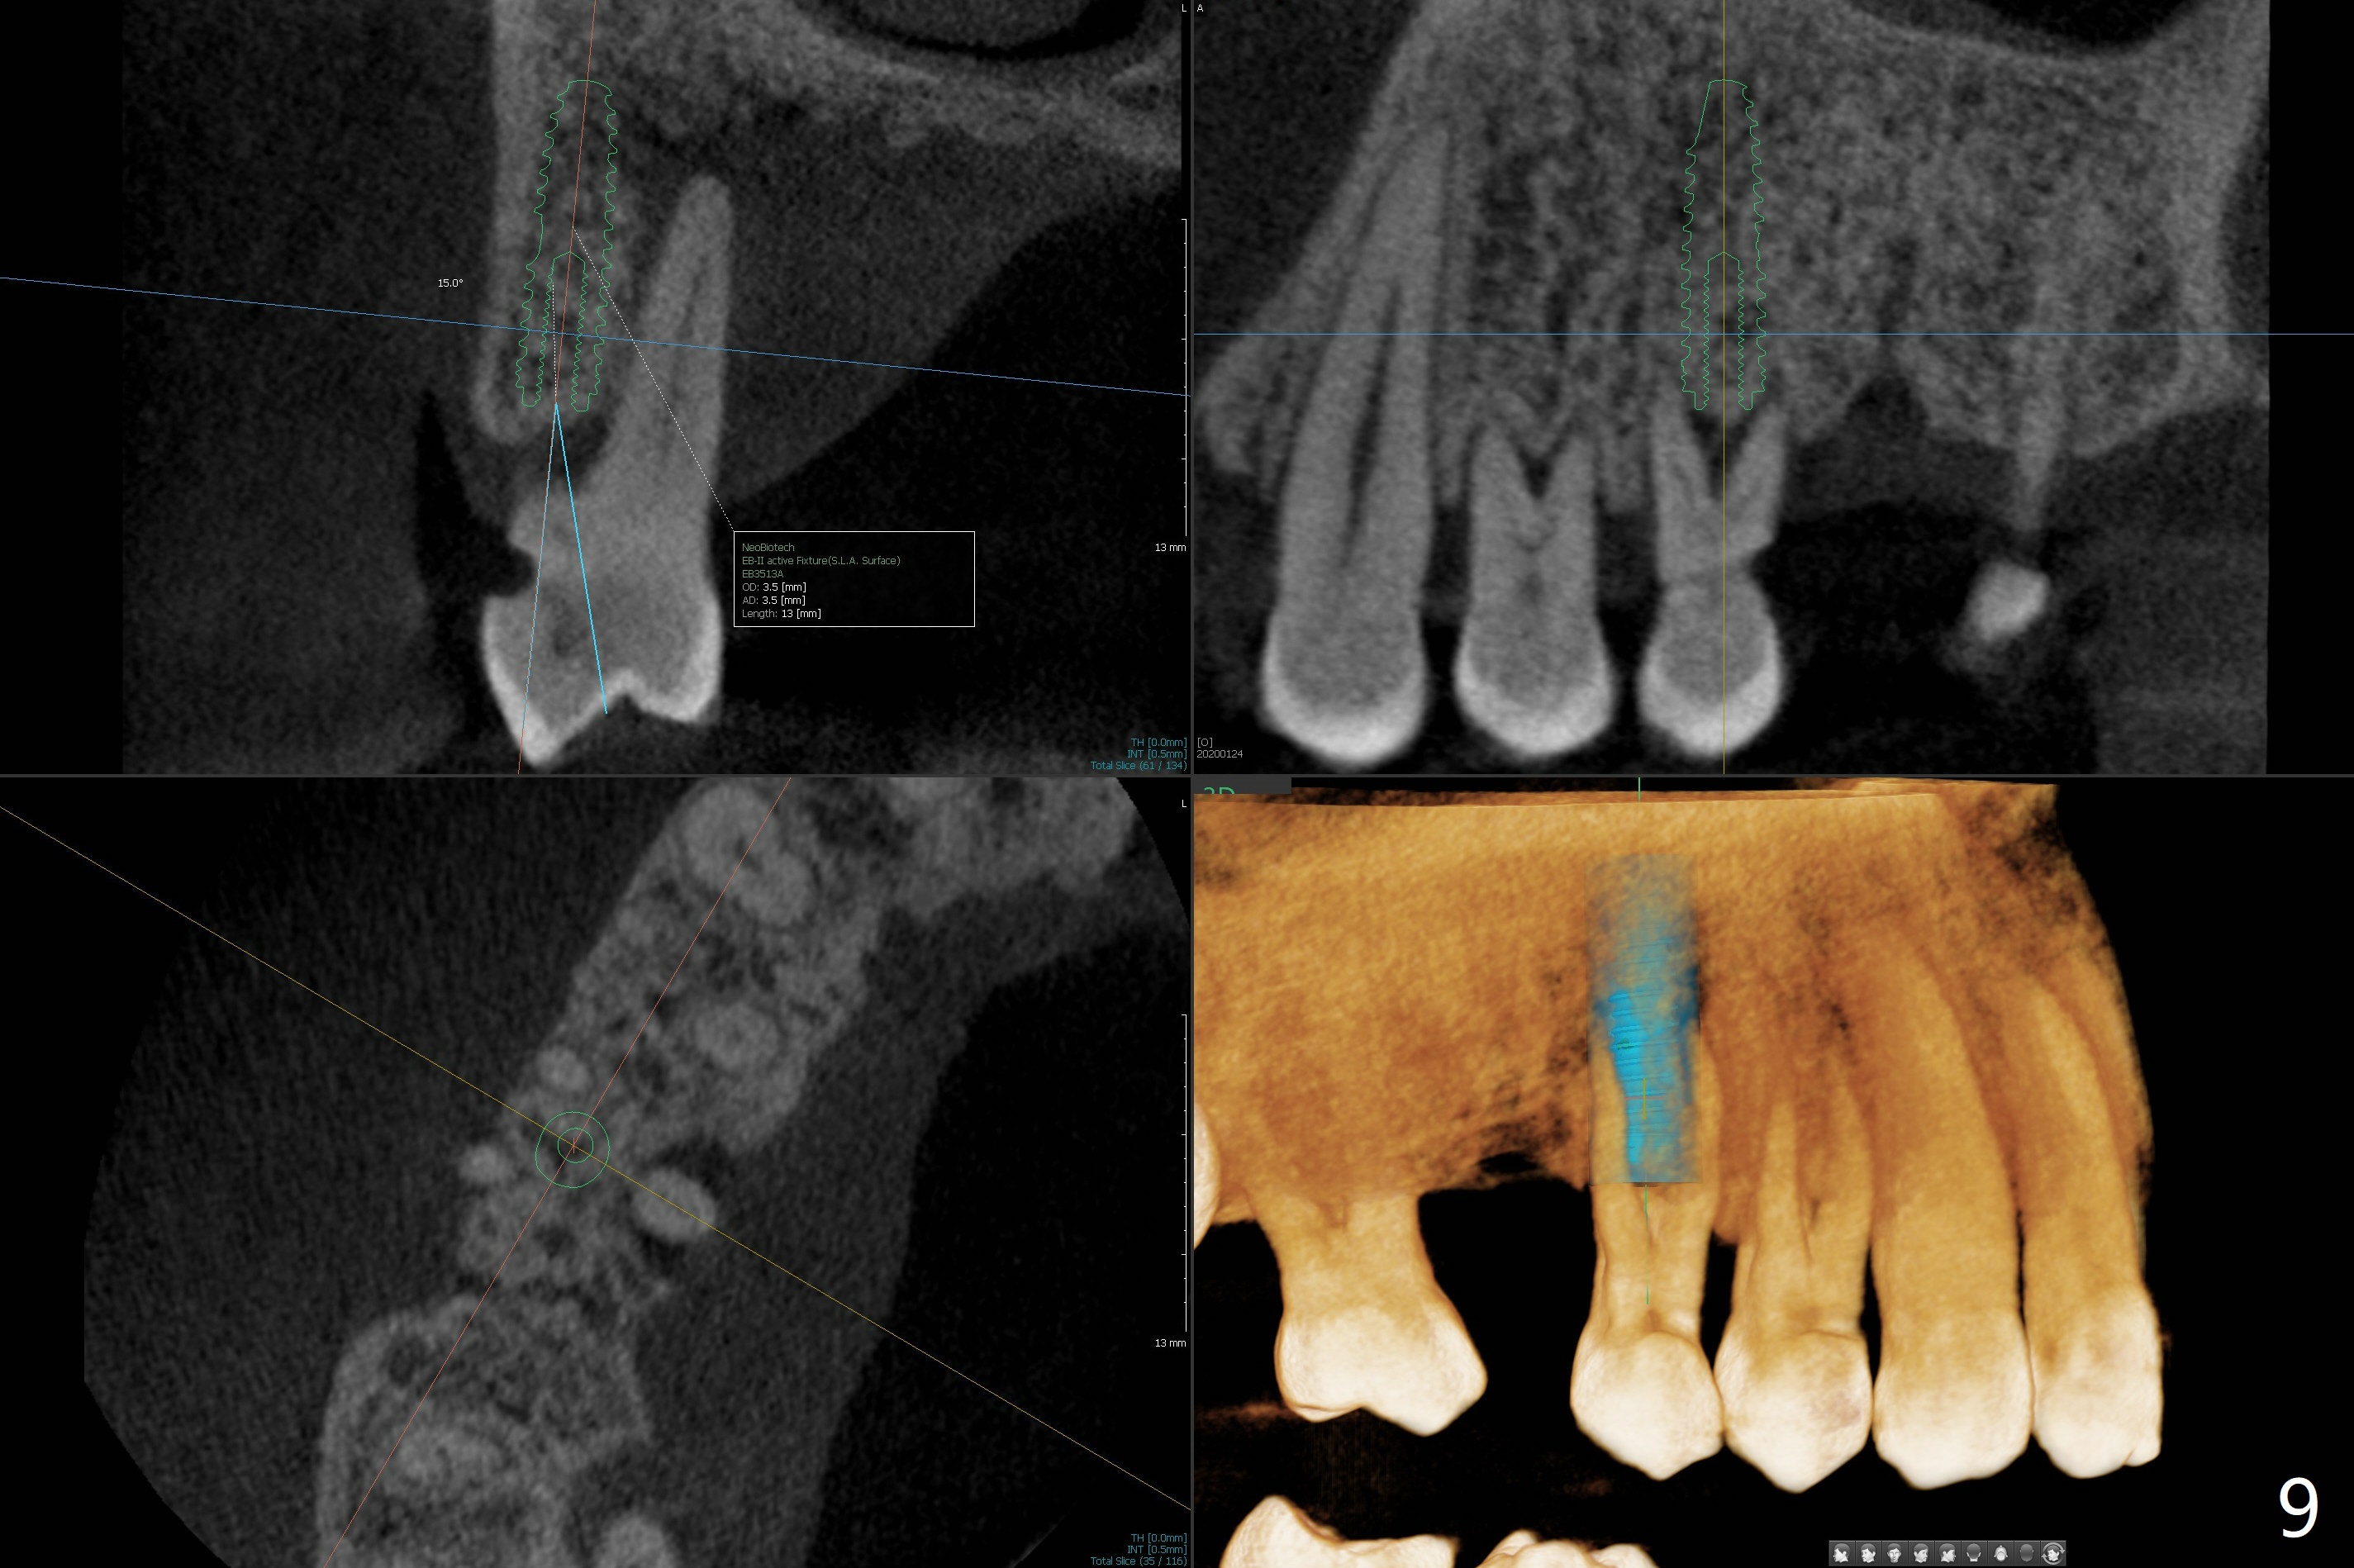

A 52-year-old man (smoker 1 ppd) has toothache in UR. The tooth #4 has severe Class V defect (Fig.1 *), periapical radio-lucency (PARL, arrow-heads) around the buccal roots and mild percu-ssion. PARL is more severe around the palatal root (Fig.2 P). Since it seems difficult to do socket preser-vation, can we do RCT to regrow bone before implant? CT coronal section shows the palatal defect of the palatal root (Fig.3,4), while sagittal one shows J defect of the palatal root, associated with root fracture (Fig.5). In fact the palatal root has transverse fracture at crestal level (Fig.6-8). The tooth #4 will be extracted for immediate implant (Fig.9,10); a 4 mm implant will be placed in the narrow space of #3 at the same time (Fig.11). The patient had symptoms consistent with aortic aneurysm. Since then smoke has been quit.